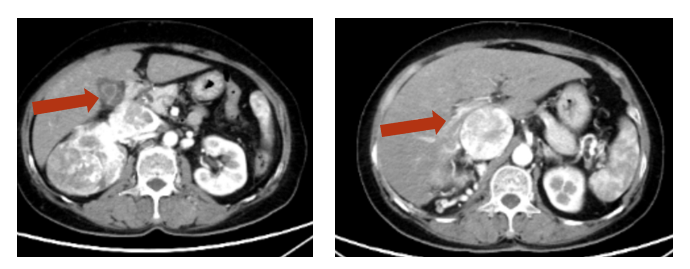

2025年2月7日胸部+全腹部(含盆腔)CT平扫+增强:右肾中上份见一类椭圆形略低密度灶,较大截面约4.6cm×3.8cm,边界欠清,增强扫描呈欠均匀轻度强化,较前变化不明显,病灶侵及部分右肾静脉-下腔静脉,以上水平下腔静脉粗大,较宽处约3.8cm,右肾恶性肿瘤并右肾静脉、下腔静脉癌栓治疗后CT所见,癌栓位于膈肌下2cm,肝静脉癌栓消失。疗效评价:PR。

图 艾托组合抗体治疗后,肝静脉癌栓消失

本病例中,这一协同效应得到了充分验证。患者在2024年11月15日启用艾托组合抗体联合伏罗尼布方案后,仅2个多月即实现肝静脉癌栓完全消失,达到PR标准;同时,下腔静脉癌栓位置稳定于膈肌下2cm,肿瘤病灶维持稳定缩小,且无新发病灶出现。这一疗效不仅体现了方案的“快速起效”特征,更证明即使在多线治疗失败的后线场景中,艾托组合抗体联合TKI仍能实现深度缓解。